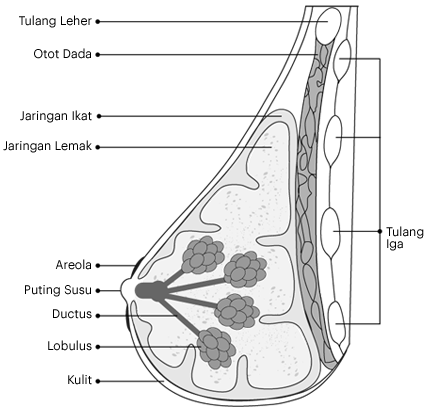

Payudara adalah jaringan massa kelenjar, lemak dan ikat (connective tissue). Payudara terdiri dari: - Kelenjar lobulus yang menghasilkan susu

- Saluran duktus yang membawa susu dari lobules ke puting susu

- Jaringan lemak dan ikat mengelilingi dan melindungi duktus dan lobules serta memberikan bentuk pada payudara

- Areola berwarna merah muda atau coklat, area melingkar disekitar puting susu yang mengandung kelenjar keringat kecil, yang melepaskan (mengeluarkan) kelembapan sebagai pelumas pada saat menyusui

- Puting susu yang merupakan area yang terletak pada bagian tengah areola darimana susu dikeluarkan

Ligamen mensuport payudara. Mereka terletak mulai dari permukaan kulit, hingga menembus dan melekat pada otot-otot yang terdapat pada dada.

Terdapat beberapa saraf besar di area payudara, termasuk saraf-saraf di dada dan lengan. Terdapat juga saraf-saraf sensorik pada kulit dada dan aksila.Gambar 1.1 menunjukkan bagian-bagian berbeda dari payudara. Otot dada utama (otot pectoralis) berada diantara payudara dan tulang rusuk di dinding dada.